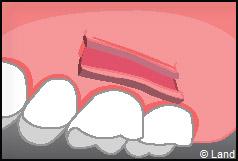

LES TECHNIQUES AVEC APPORT DE GENCIVE OU « GREFFE DE GENCIVE » :

Elles font appel à un prélèvement sur le patient à un endroit où elle est en excès, qui est ensuite posé sur la récession.

Les greffes épithélio-conjonctives :

Elles sont pratiquées pour des zones non esthétiques de la cavité buccale, à cause de l’aspect « rustine» que la cicatrisation leur confère.

Destinées aux zones esthétiques, elles consistent à prélever la partie profonde du palais (site donneur).